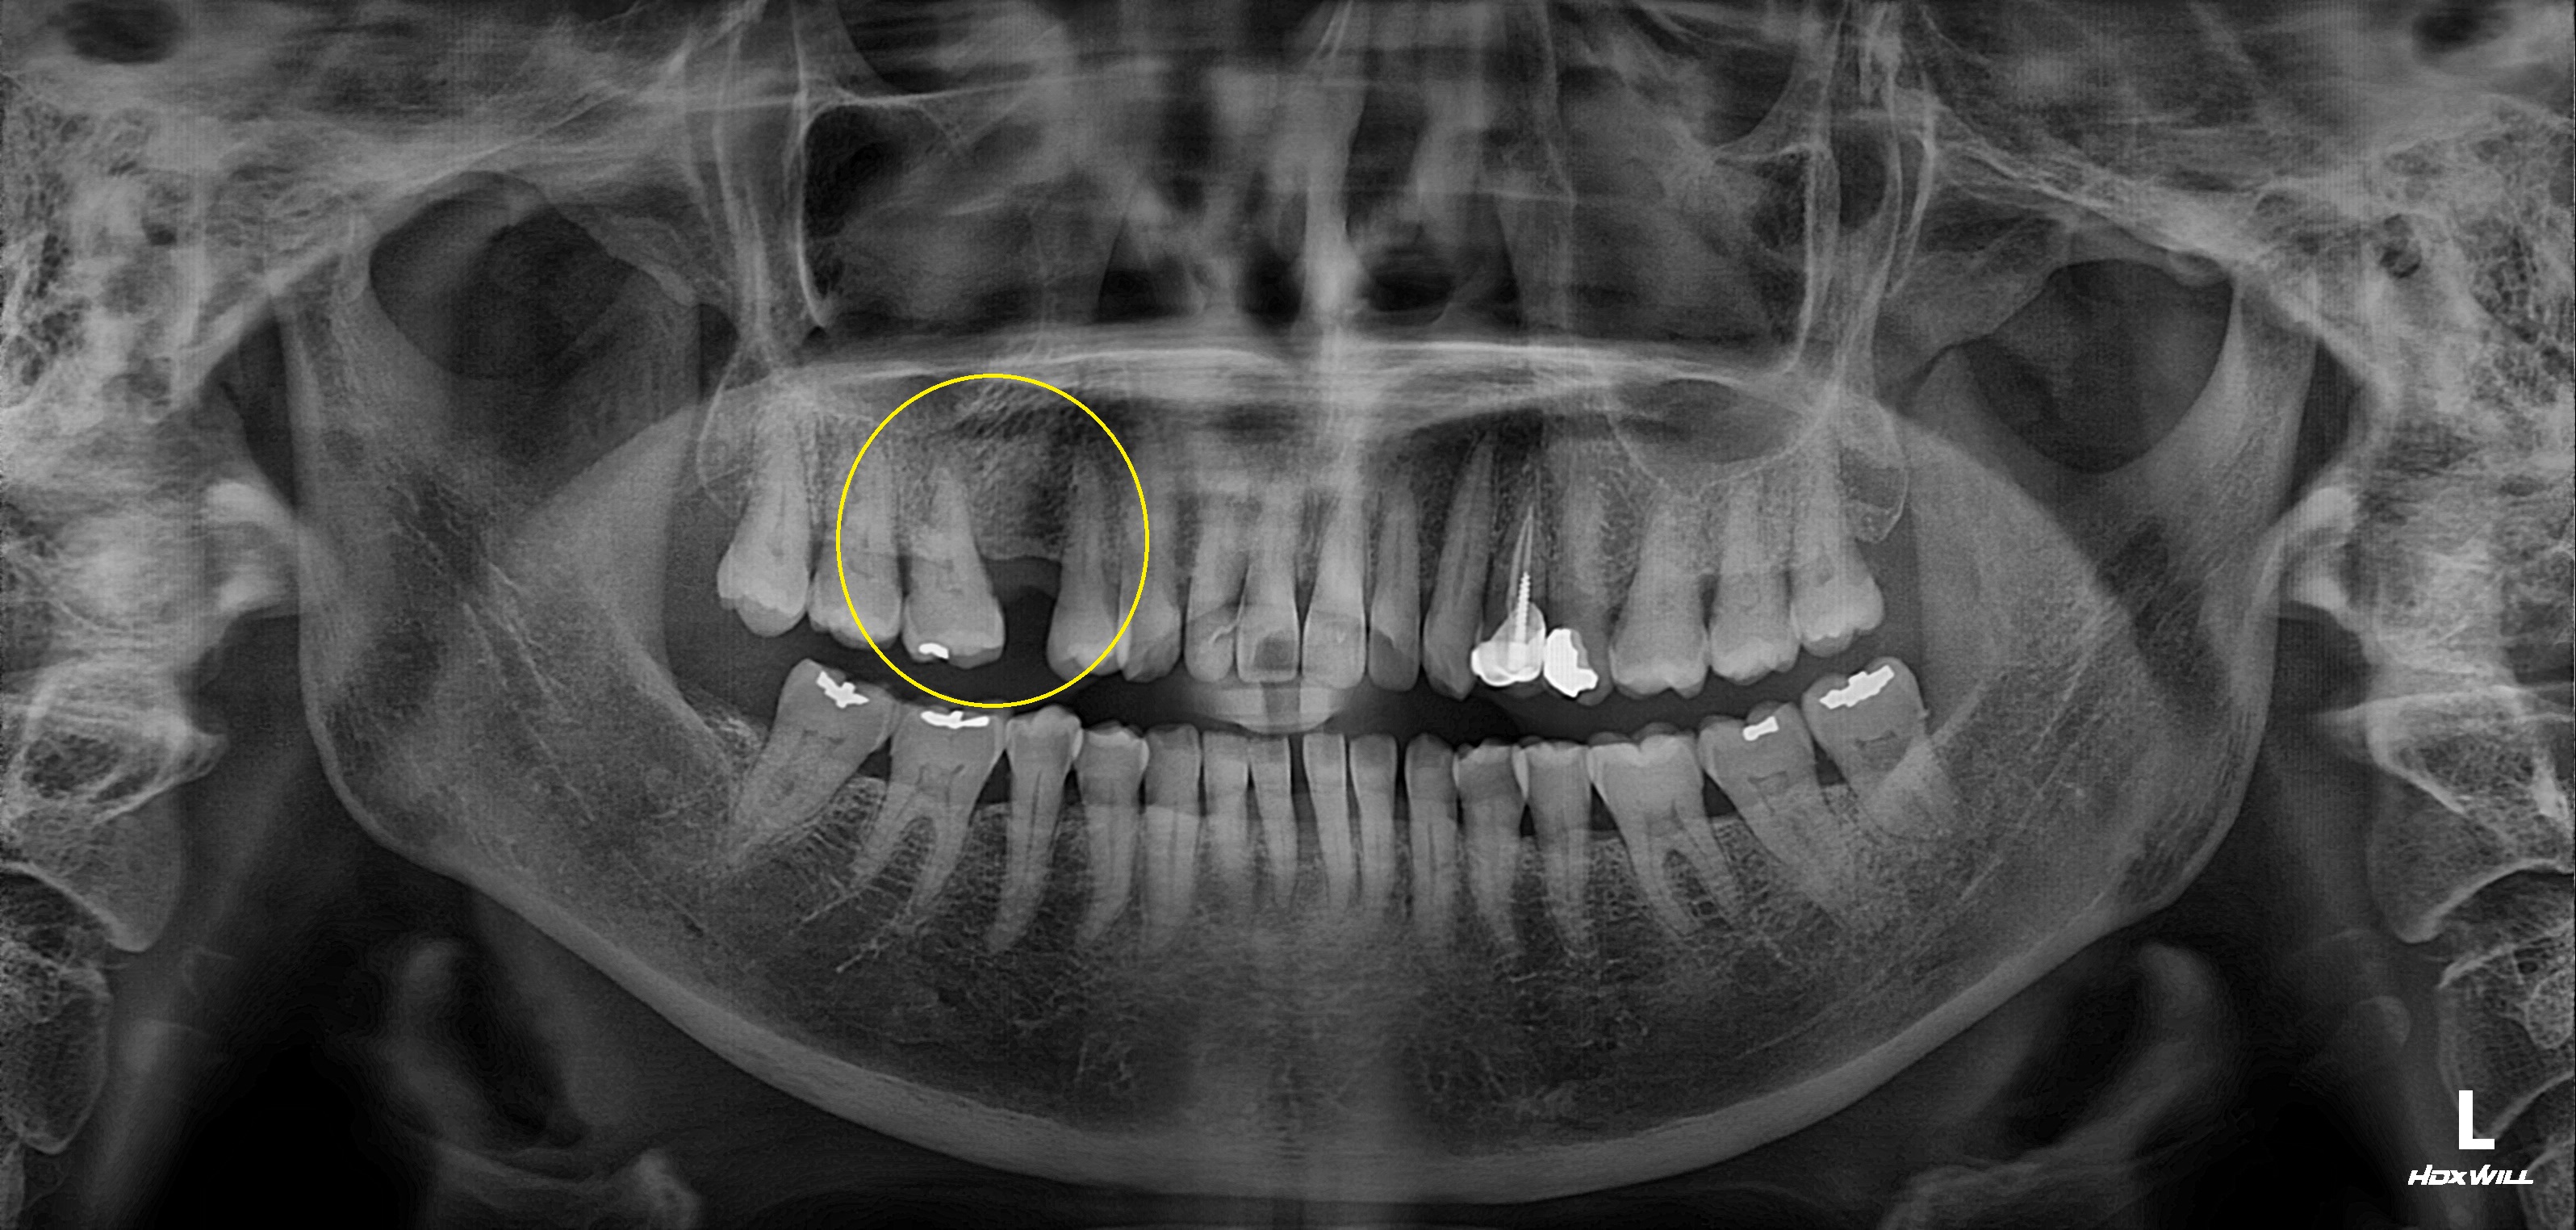

완전매복치 발치 사례

전후사진

수술 전

수술 후